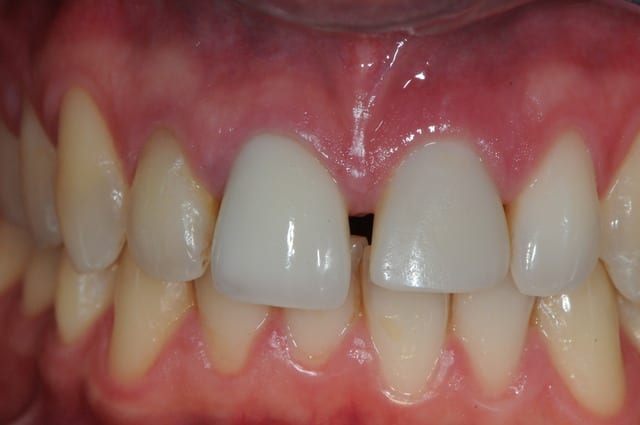

voici des news du deuxième cas clinique.

nous sommes à j+7

je pense que la gencive devrait encore remonter dans les 3 prochains mois...

J+7 ?

Super beau !